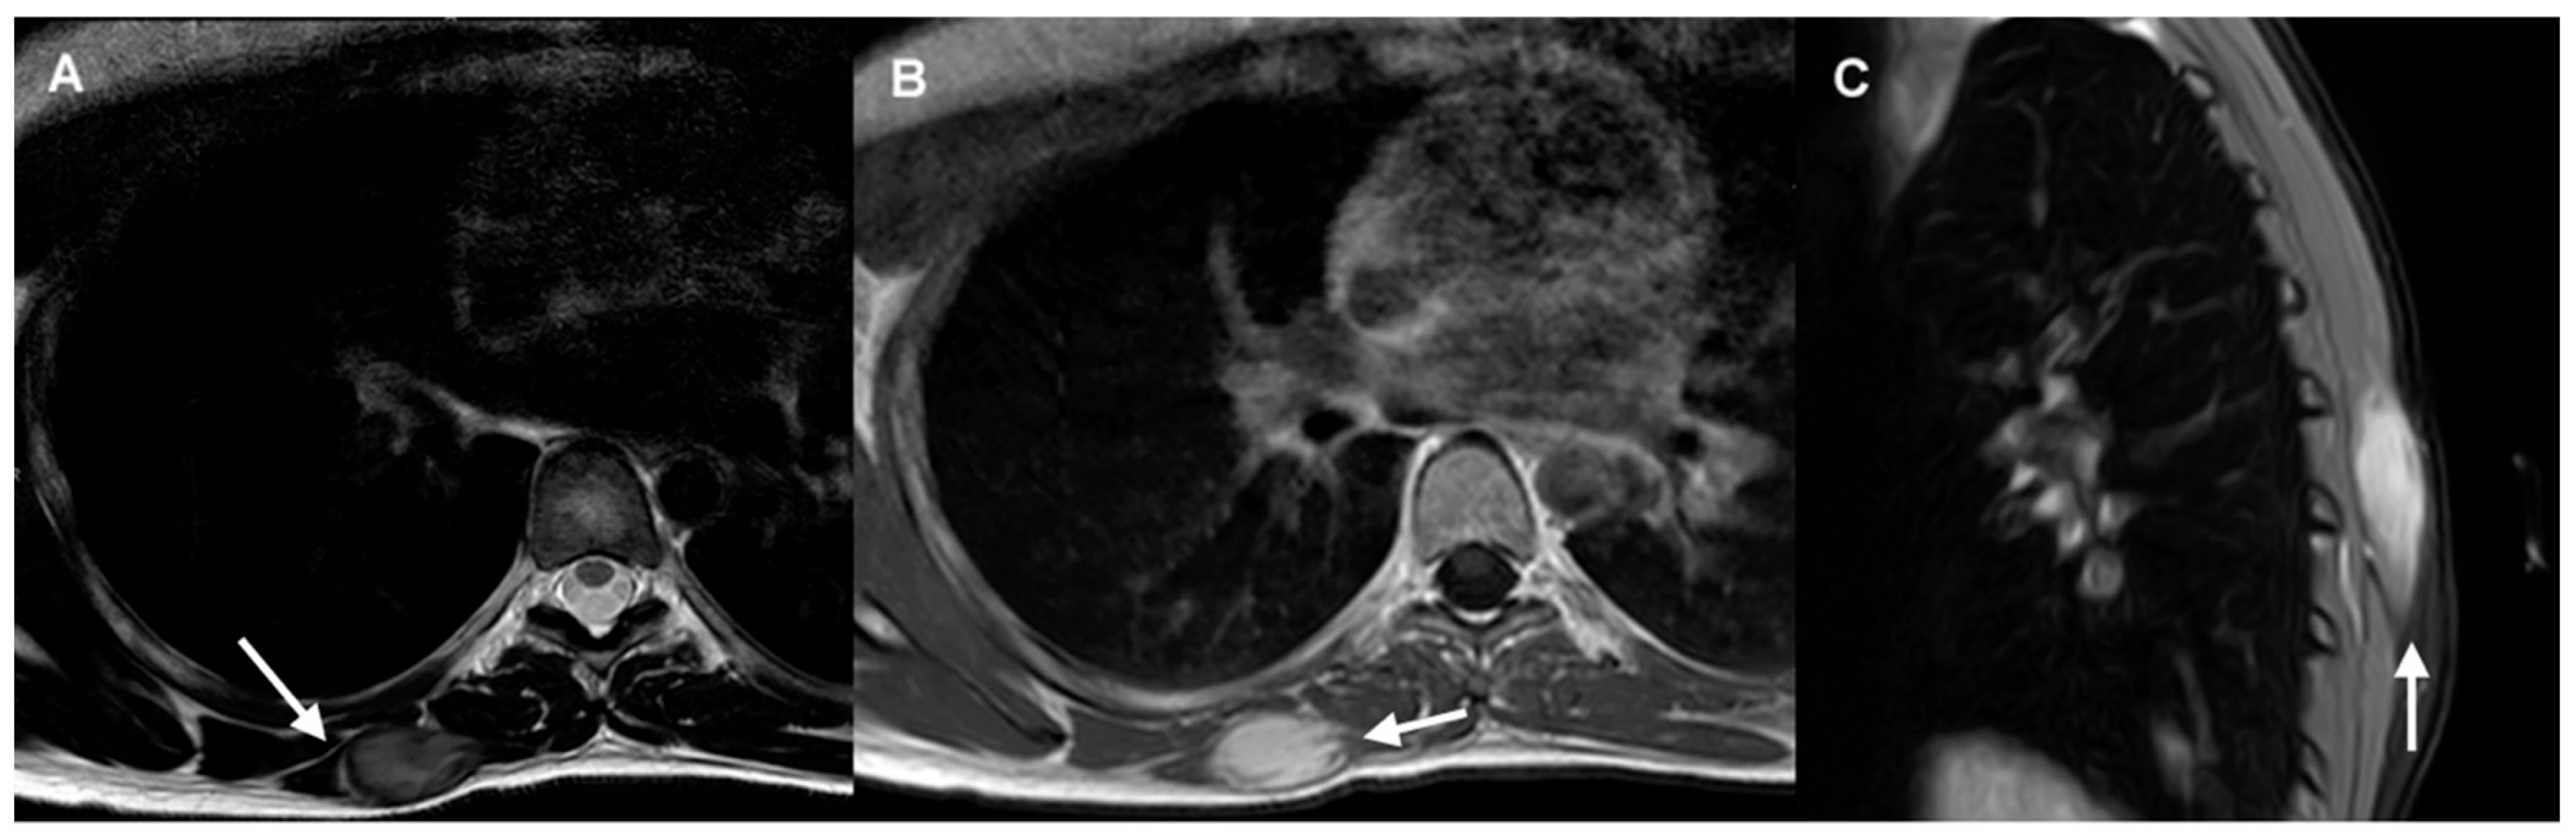

3.1. Imaging Diagnosis

- CT and MRI are the imaging modalities of choice for treatment planning, image-guided procedures, and follow-up in patients with DTs (IV, B).

- MRI is considered the optimal imaging modality for evaluating extra-abdominal DTs (IV, B).